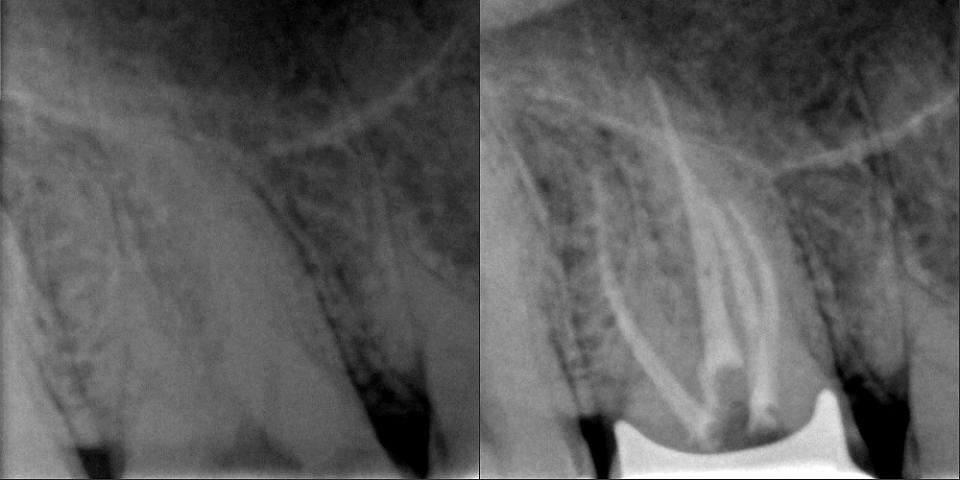

paraschyk1 Опубликовано 16 октября, 2015 Автор Опубликовано 16 октября, 2015 Выпал недавно реставрированный жевательный семерка вместе со штифтами. Т.е. там остались одни корни, над десной ничего от зуба нет. Было 2 штифта, реставрация + обычная простая коронка сверху. Все это аккуратно выпало. Один стоматолог говорит, что даже браться не будет, мол через годик снова отвалится, только вырывать. Другой говорит, что здоровый корень, какой нафиг рвать, только делать. Ниже вариант спасения зуба,когда полная жопа. Такой зуб может бегать пять лет и более.

paraschyk1 Опубликовано 13 декабря, 2015 Автор Опубликовано 13 декабря, 2015 Починил форумчанена после неудачного лечения.